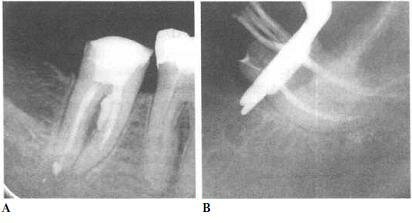

Перфорация пульпы

Перфорация пульпы 100 фотографий